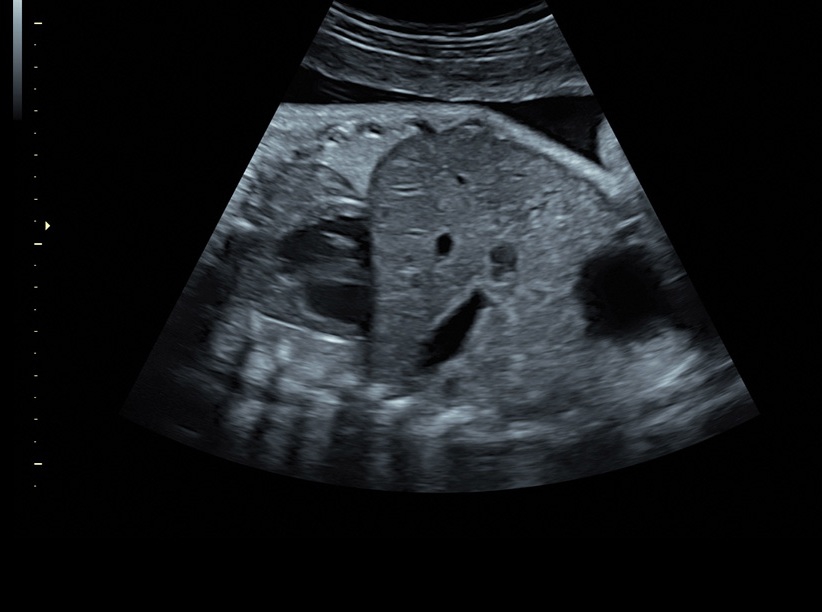

• Сложные инструменты для оценки качества плода: Сканер оснащен инновационными инструментами, позволяющими проводить детальную оценку состояния плода, включая его сердечную деятельность, анатомию и кровоток.

• Программа для исследований сердца плода с возможностью цветовых допплеровских и ангиографических исследований на основе анализа пространственно-временной корреляции изображений (STIС)